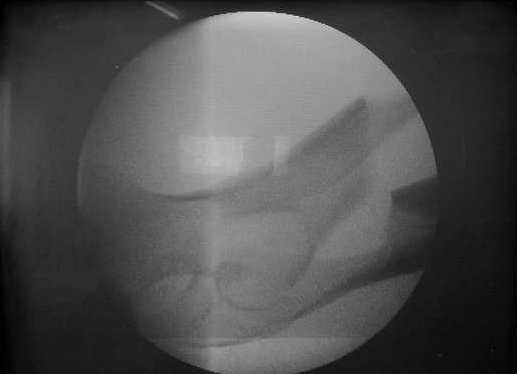

27 марта выполнено удаление блокирующих винтов (сломанный винт пришлось высверливать цапфен-бором), сломанного штифта (дистальный фрагмент удален через канал, образованный разверткой из коленного сустава - image 4),

рассверливание костно-мозгового канала, реостеосинтез штифтом UFN (при проведении штифта в дистальном отломке мы использовали поляризующий винт, диаметр штифта 10 мм). После операции в связи гемартрозом дважды (на 1 и 3 сутки) выполняли пункцию коленного сустава. Сейчас признаков скопления жидкости в полости сустава нет. Послеоперационные рентгенограммы - images 5, 6, 7.